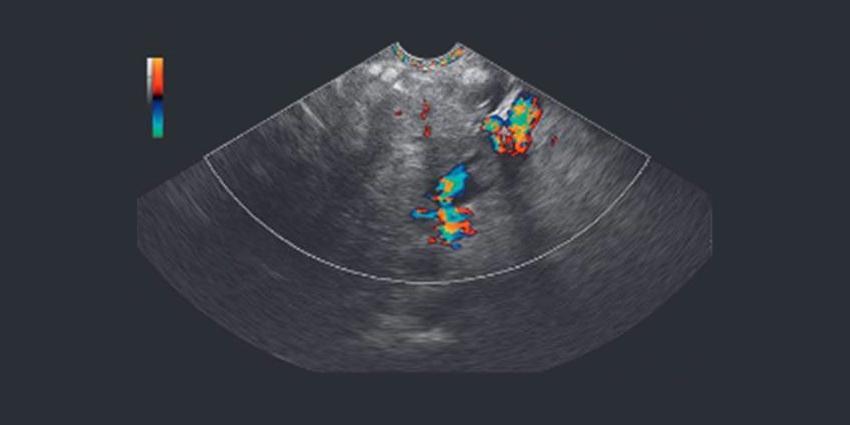

Modern ultrasound endoscope EG-3270UK guarantees high accuracy of Fine Needle Aspiration (FNA), as well as excellent image quality. These two possibilities bring the development of medicine to a new level, enabling physicians to perform a wide range of procedures.

Canadian professor of medicine claims that this device can be also used for lung cancer detection. Moreover, ultrasound endoscope is more effective than other devices because with its help the physician can immediately evaluate the structure of the malignancy, its spread and other characteristics. The images quality makes it possible to be 100 percent sure that the diagnosis is precise.